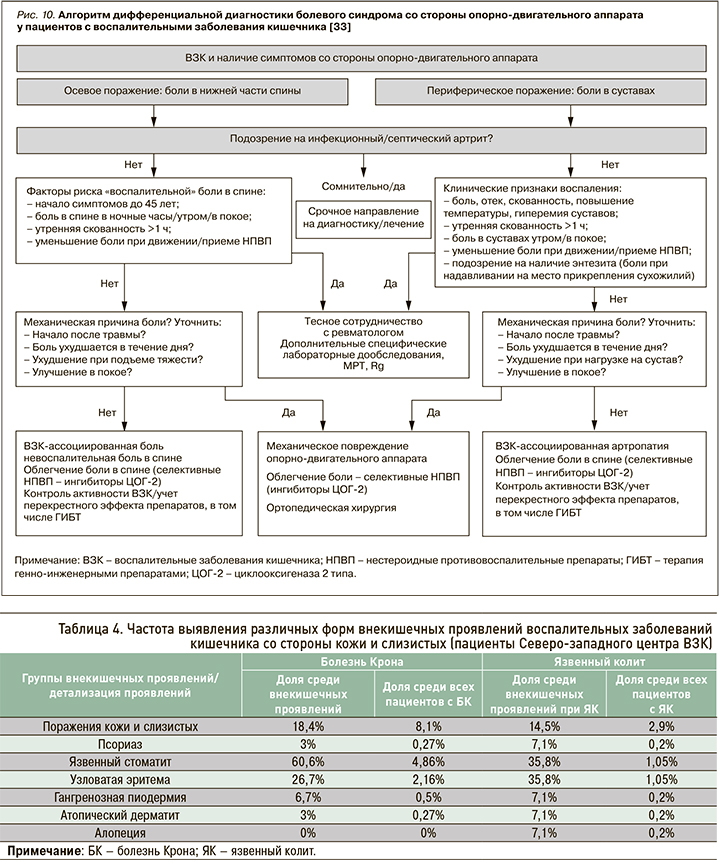

Периферические ВЗК-ассоциированные артропатии могут носить «невоспалительный» характер, т.е. протекать без синовита (см. рис. 8). Частота таких «невоспалительных» артропатий, по данным разных наблюдений, составляет от 5 до 16%, но на сегодняшний день остается неясной их взаимосвязь с активностью основного заболевания [9, 41]. Кроме того, ВЗК-ассоциированные «невоспалительные» артропатии необходимо дифференцировать с артралгиями на фоне отмены глюкокортикостероидов (ГКС), парадоксальными артралгиями, вызванными приемом тиопуринов или препаратов анти-ФНО, ведолизумаба, устекинумаба (рис. 10) [43, 44].

ПОРАЖЕНИЯ КОЖИ ПРИ ВОСПАЛИТЕЛЬНЫХ ЗАБОЛЕВАНИЯХ КИШЕЧНИКА

По данным Северо-западного регистра ВЗК, кожные проявления занимают 2-е место по частоте выявления среди всех внекишечных проявлений ВЗК (18,4 и 14,5% у пациентов с болезнью Крона и язвенным колитом соответственно); при этом они в 2,5 раза чаще отмечались у пациентов с болезнью Крона (8,1%) по сравнению с язвенным колитом (2,9%). Обращает на себя внимание большая частота язвенного стоматита и узловатой эритемы у пациентов с болезнью Крона и относительно одинаковая для остальных кожных проявлений (табл. 4).